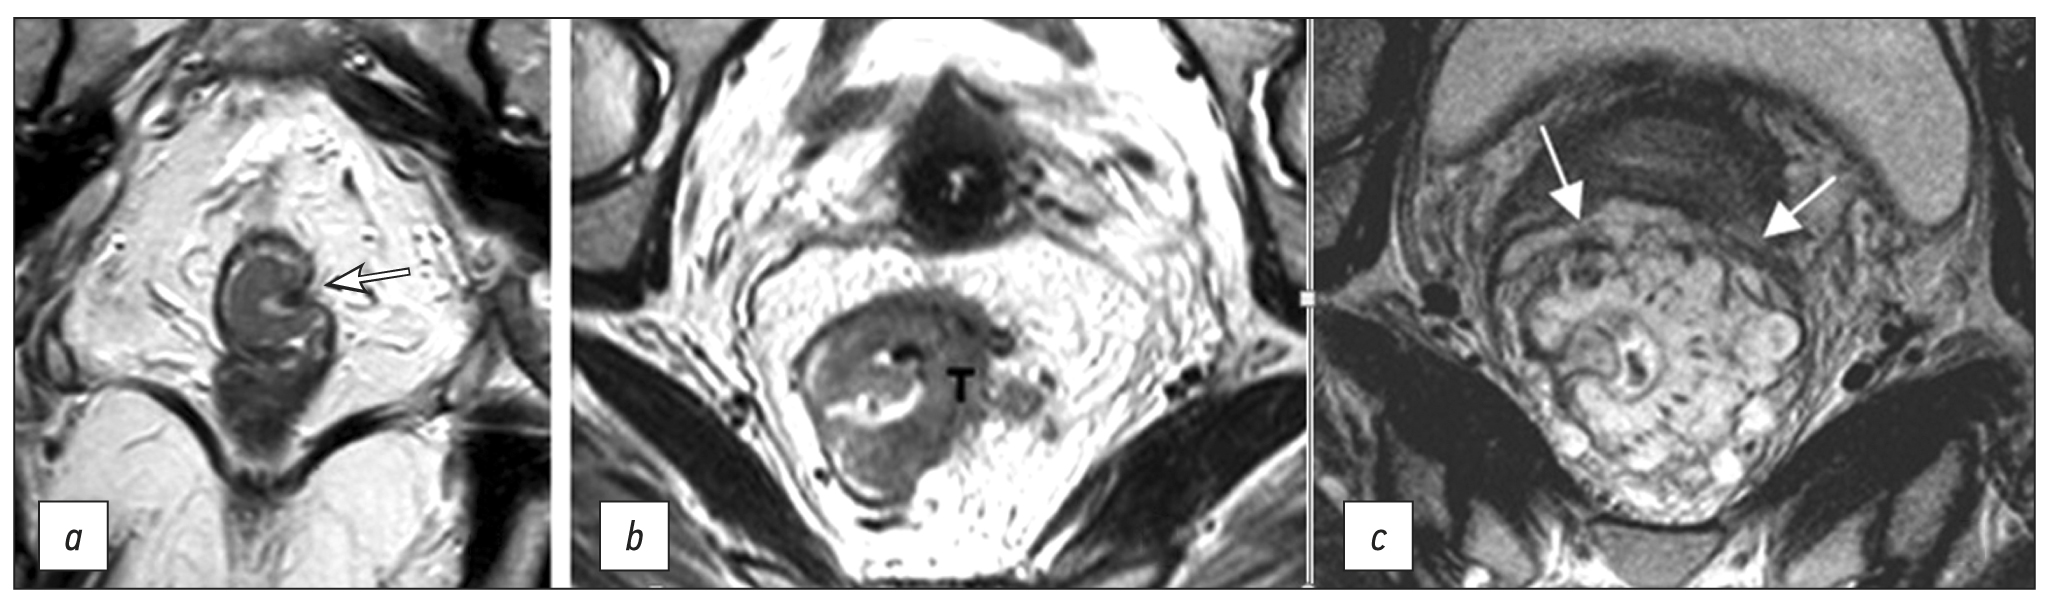

The anal margin refers to the anocutaneous line, the junction of the anoderm with the perianal skin, corresponding to the distal edge of the internal sphincter of the anal canal/intersphincteric groove on sagittal MRI (Fig. 1). From this level, the distance to the lower edge of the tumor is measured on sagittal T2-weighted images along the center of the lumen of the anal canal and rectum [6].

The anorectal junction is the connection between the anal canal and the rectum, corresponding to the upper edge of the puborectalis muscle, clearly defined on T2-WI in the coronal plane, or the anorectal angle, defined on T2-WI in the sagittal plane (Fig. 1). The distance from the anorectal junction to the inferior margin of the tumor is important for surgery planning and should be indicated in the diagnostic report [6].

The anal sphincter complex includes the internal and external anal sphincters and the puborectalis muscle (Fig. 1).

Fig. 1. MRI anatomy of the rectum on T2-WI. (a) Sagittal plane: anal edge (intersphincteric groove; dotted line); anorectal junction (angle) at the level of the upper border of the internal sphincter of the anal canal (white arrows); transitional fold of the peritoneum at the lower point of attachment of the pelvic visceral peritoneum to the rectal wall (asterisk); peritonealized part of the rectum (black arrows). (b) Coronal plane: 1, internal sphincter of the anal canal; 2, intersphincteric space; 3, deep portion of the external sphincter; 4, superficial portion of the external sphincter; 5, subcutaneous portion of the external sphincter; 6, puborectalis muscle; 7, elevator muscle of anus (levator ani). (c) Axial plane: 1, intestinal lumen; 2, mucous membrane; 3, submucosal layer; 4, muscle layer; 5, mesorectal tissue; 6 mesorectal fascia.

The internal anal sphincter is a continuation of the internal circular muscle layer of the rectum, comprising smooth muscle tissue. On MRI, it is determined by a significant thickening of the intrinsic muscle layer of the wall at the level of the anal canal (Fig. 1). The signal from the internal sphincter on T2-weighted images is slightly higher than that of the external sphincter, and with contrast enhancement, it appears more intense.

The external anal sphincter is a striated muscle, which is a continuation of the puborectal muscle, divided into three layers, such as the subcutaneous circular layer, superficial ellipsoidal layer, connected to the coccyx, and deep layer, closely connected with the puborectalis muscle (Fig. 1).

The intersphincteric space is a connective-cellular tissue space that separates internal and external anal sphincters and is characterized by a high signal on T2-WI (Fig. 1).

Mesorectal fascia is a thin fascial sheath that limits the rectum and the surrounding fatty tissue. On T2-WI, it appears as a hypointense circular line (Fig. 1). In men, the mesorectal fascia in front merges with the Denonvilliers’ fascia, while in women, it merges with the rectovaginal fascia (septum). At the back, it connects with the presacral fascia; it completely surrounds the rectum only to the level of the transitional fold of the peritoneum with its lateral and posterior parts above and only the posterior rectum at the level of the upper ampullary. Caudally, the mesorectal fascia passes into the intersphincteric space.

The muscular layer of the rectum consists of an inner circular and outer longitudinal layer, which are defined as a single hypointense layer on T2-weighted MRI images, limited internally by a hyperintense submucosal layer and externally by hyperintense mesorectal tissue (Fig. 1).

The elevator muscle of the anus (m. levator ani) is a muscle complex (Fig. 1), consisting of the puborectalis, pubococcygeus, iliococcygeus, and anal-coccygeal fibrous muscles and anococcygeal ligament. Tumors infiltrating the elevator muscle of anus are classified as T4b.

The transitional fold of peritoneum is formed at the point of transition of the peritoneum from the pelvic organs to the rectal wall, with the lower point of attachment along the anterior wall of the intestine and obliquely going up the side walls. It separates the peritonized and non-peritonized parts of the rectum. On T2-WI, it appears as a hypointense line, displaying a V-shape in the axial plane, and passes from the apex of the seminal vesicles (in men) or from the body of the uterus (in women) in the sagittal plane (Fig. 1). Lymphatic drainage from tumors located above the transitional fold of the peritoneum mainly occurs through the upper rectal and lower mesenteric lymph nodes. Tumors below the transitional fold of the peritoneum can drain through the internal iliac and obturator lymph nodes. When describing MRI findings, it is recommended to indicate the position of the tumor relative to the transitional fold of the peritoneum (completely below/crosses/completely above) [6].